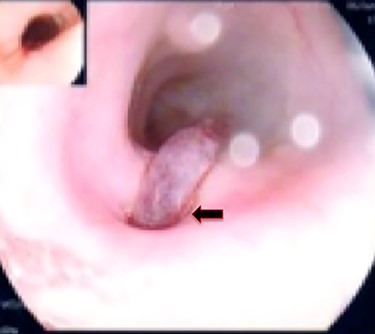

A 36-year-old male, involved in a minor motor vehicle accident while driving his car. He lost consciousness following a sudden onset of transient loss of vision which was not associated with palpitation or dizziness. His previous medical history revealed arterial hypertension and a corrected aortic coarctation with interposition graft at the age of 14. Pan CT scan was unremarkable except for thickening of the desending throacic aorta. His white blood count was very high (68 000 per cubic millimeter of blood). One day after the car accident, he developed nausea, hematemesis and melana. Upper GI endoscopy revealed blood in the stomach and distal esophafgus with no identifiable source of bleeding (Fig. 6). The patient developed massive hematemsis with hypotension requiring intubation and resuscitation. Another CT scan showed air pocket around distal aorta and contrast extravasation to the esophagus (Fig. 7). Another endoscopy revealed distal esophageal ulcer with clot extending toward the stomach (Fig. 8). AEF was suspected and then confirmed by aortogram. The fistula was treated by TEVAR (20 mm × 11.5 cm Valiant covered stent - Medtronic company, USA) followed by fully covered esophageal stent in the middle of the esophagus (Fig. 9).

Second upper endoscopy fresh bleeding from the distal esophagus and after washing the blood an adherent clot extending from an ulcer going down into the stomach can be seen.